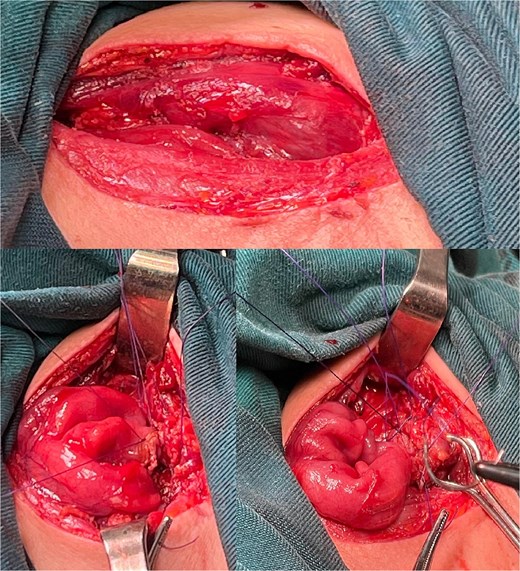

The right colon was mobilized using a standard Cattell–Braasch maneuver. Intraoperative assessment revealed the absence of the right colic artery; perfusion relied on the ileocolic artery and the right branch of the middle colic artery via a well-formed marginal artery of Drummond (Fig. 2). Temporary occlusion of the ileocolic vessels confirmed adequate collateral flow (Fig. 3). The terminal ileum was transected ~3 cm proximal to the ileocecal valve, and an incidental appendectomy was performed.

Confirmation of collateral vascular flow in the right colon (arrow shows ileocolic artery).

In our case, the absence of the right colic artery and dominant supply via the ileocolic and middle colic arteries was confirmed intraoperatively, with a robust marginal artery of Drummond ensuring perfusion. This eliminated the need for supercharging, which may be reserved for questionable vascularization or very long conduits [7, 12, 15]. The posterior mediastinal route was selected before retrosternal and subcutaneous routes due to prior resection of the native esophagus and stomach, providing a natural and anatomical path [9]. This route minimizes redundancy, allows for smoother conduit passage, and reduces the risk of compression depending on the patient’s anatomy [5, 11, 15].